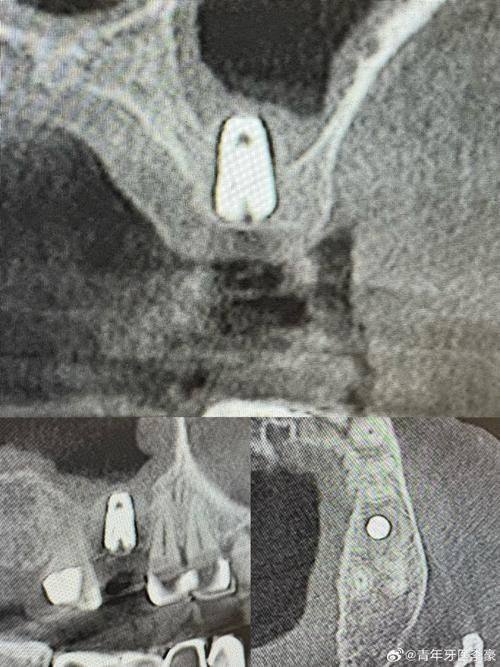

上颌窦提升术:专门解决上颌骨骨量不足的种植难题,通过专精的手术技术提升上颌窦空间,为种植体创造充足的骨支持条件,保护种植牙手术的顺利开展与长期稳定性。